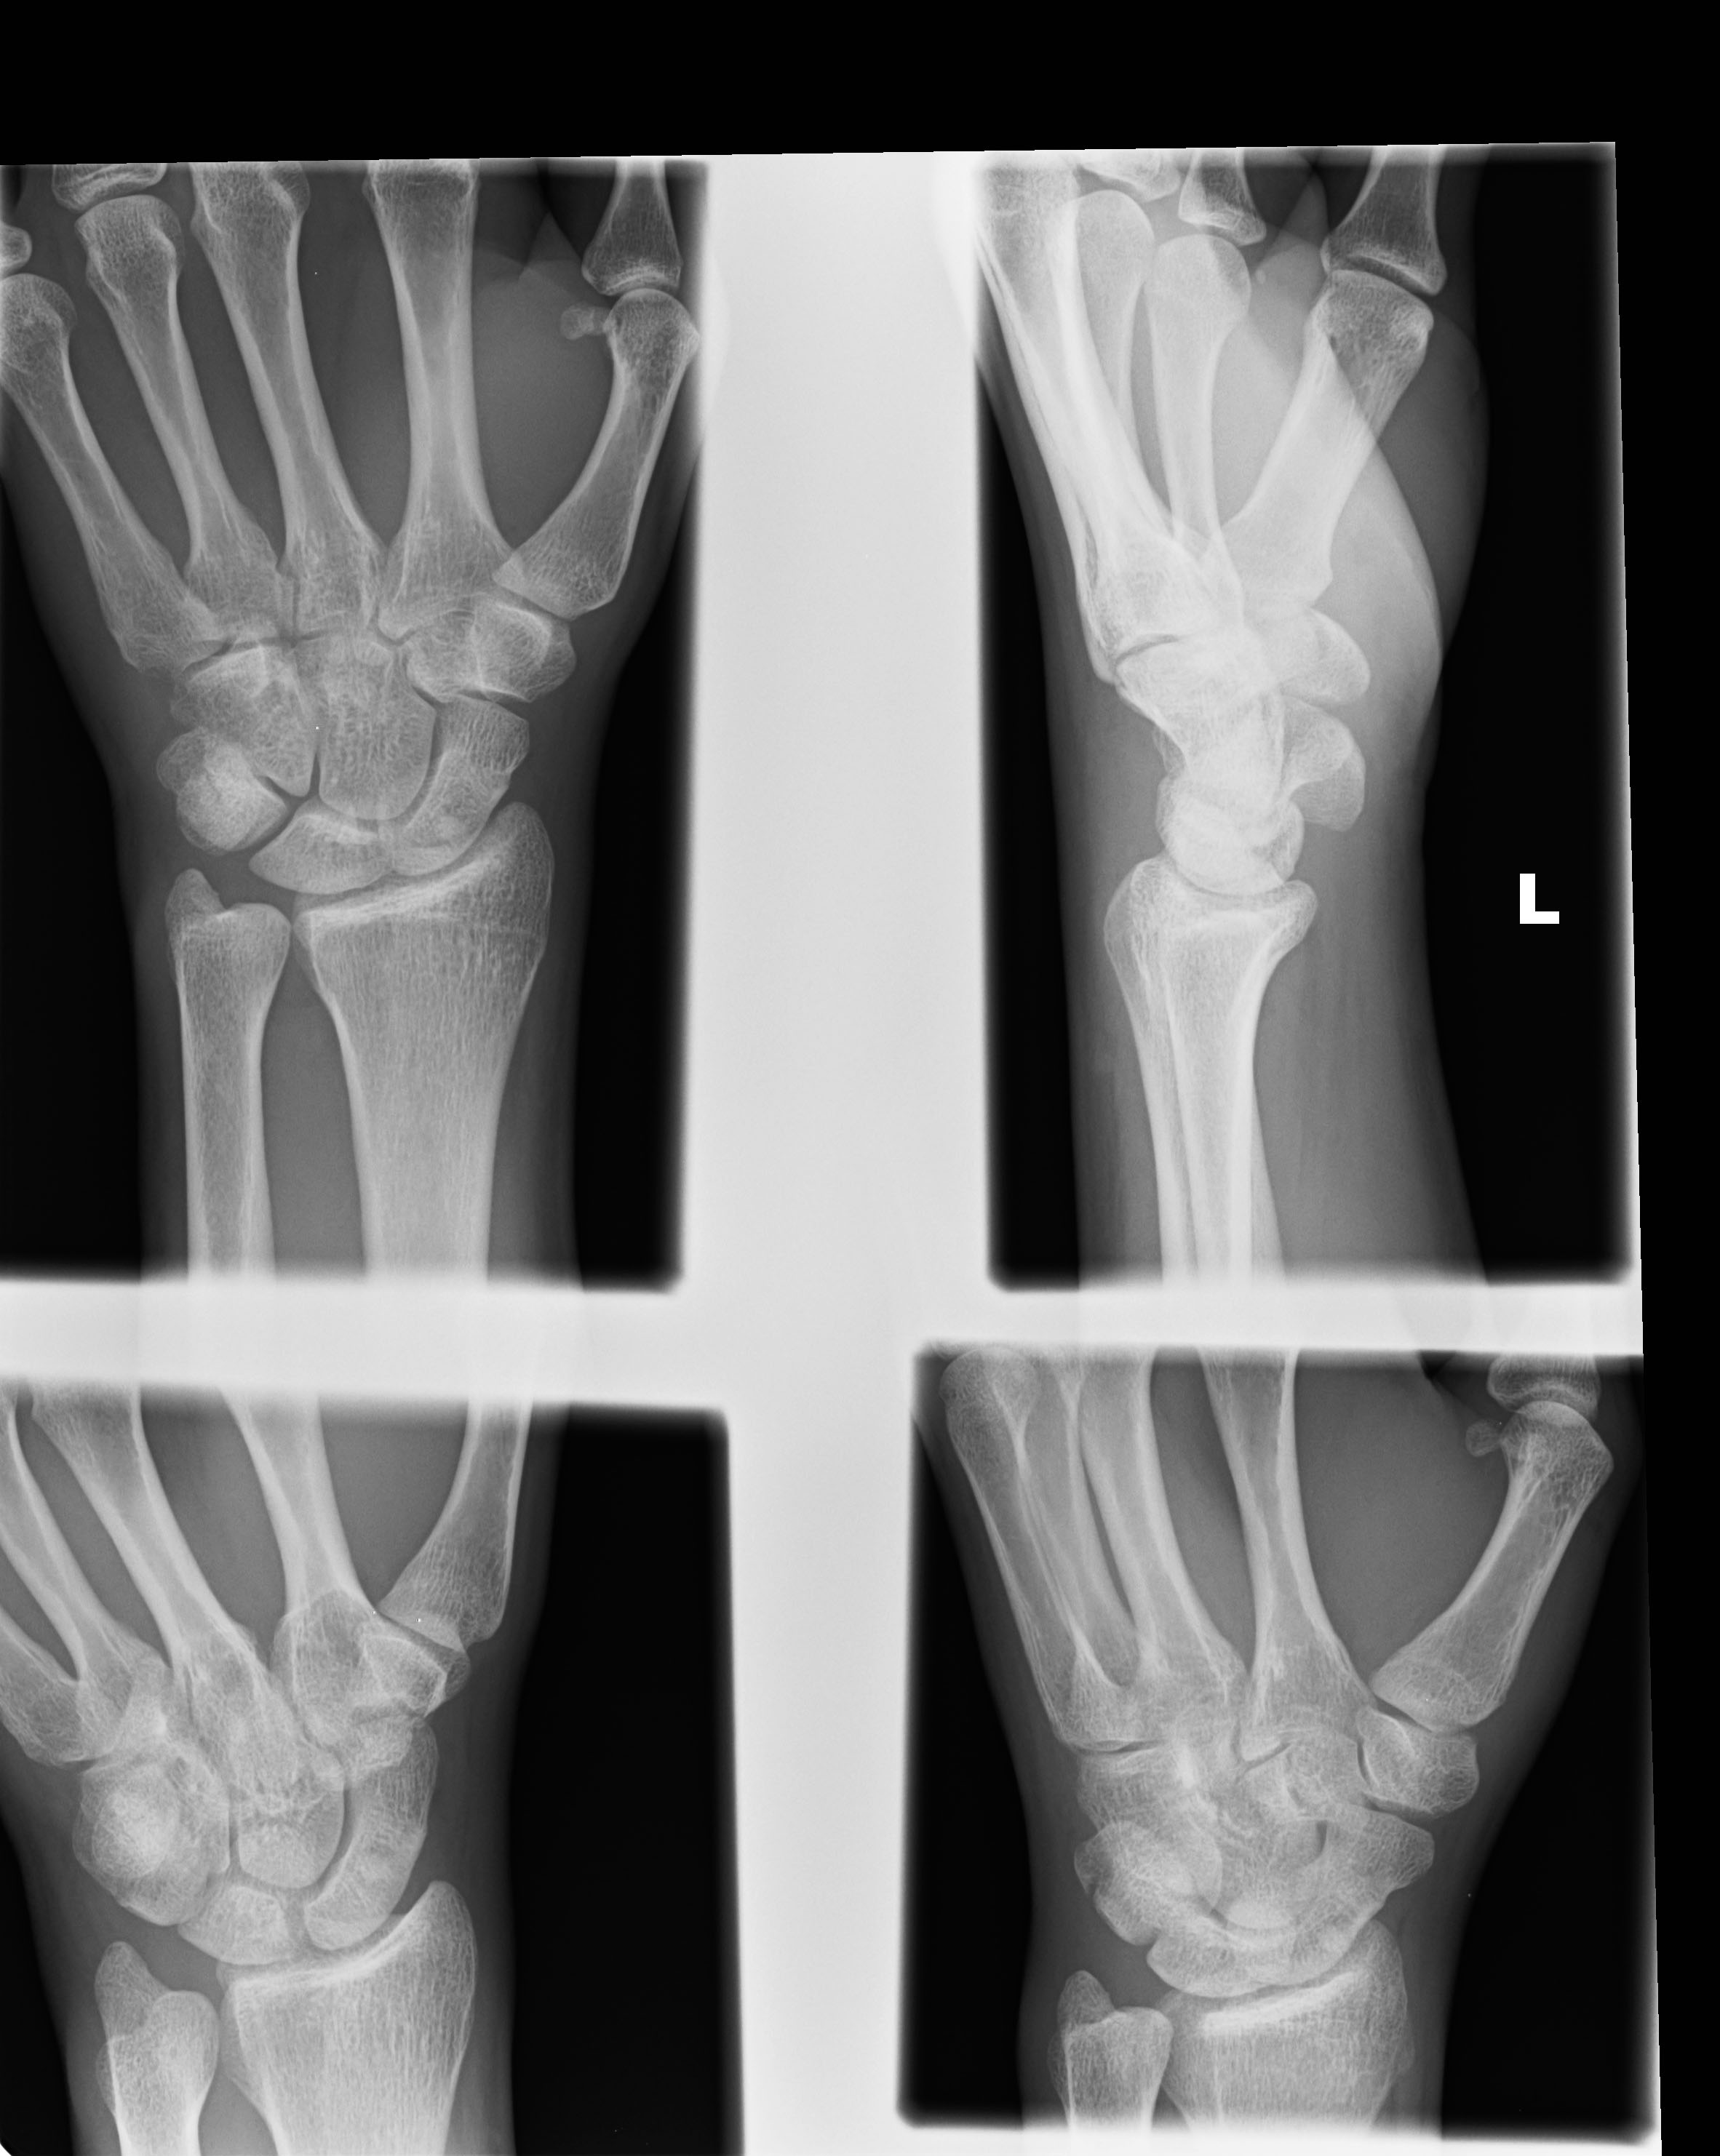

| 23 |

Abnormal fr pisiform |

Abnormal Left triquetral fracture |

Correct |